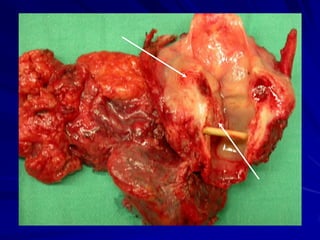

口腔癌晚期症狀

腫瘤已侵犯深層肌肉及血管侵犯,或向外

侵犯至皮膚表層。

淋巴組織轉移到頸部淋巴結,最後也可能

會轉移到身體其他器官。

顏面骨外觀變形、腫脹、腫瘤出血。